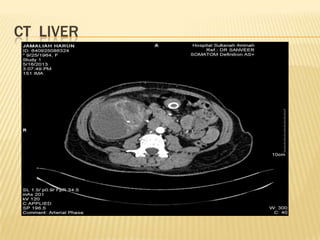

CT LIVER

IMAGING  Usg HBS Huge heterogenous cystic mass in the right liver lobe measuring > 20.5cm X 12cm.Presence of gallstone in GB.IHD and CBD not dilated Imp : suggestive of hydatid cyst with diffrential of amoebic liver abcess *** further history : h/o of multiple visits to egypt within past few years. Last visit was in feb 2013 whr she took local salad dish with grilled fish and snails delicacies